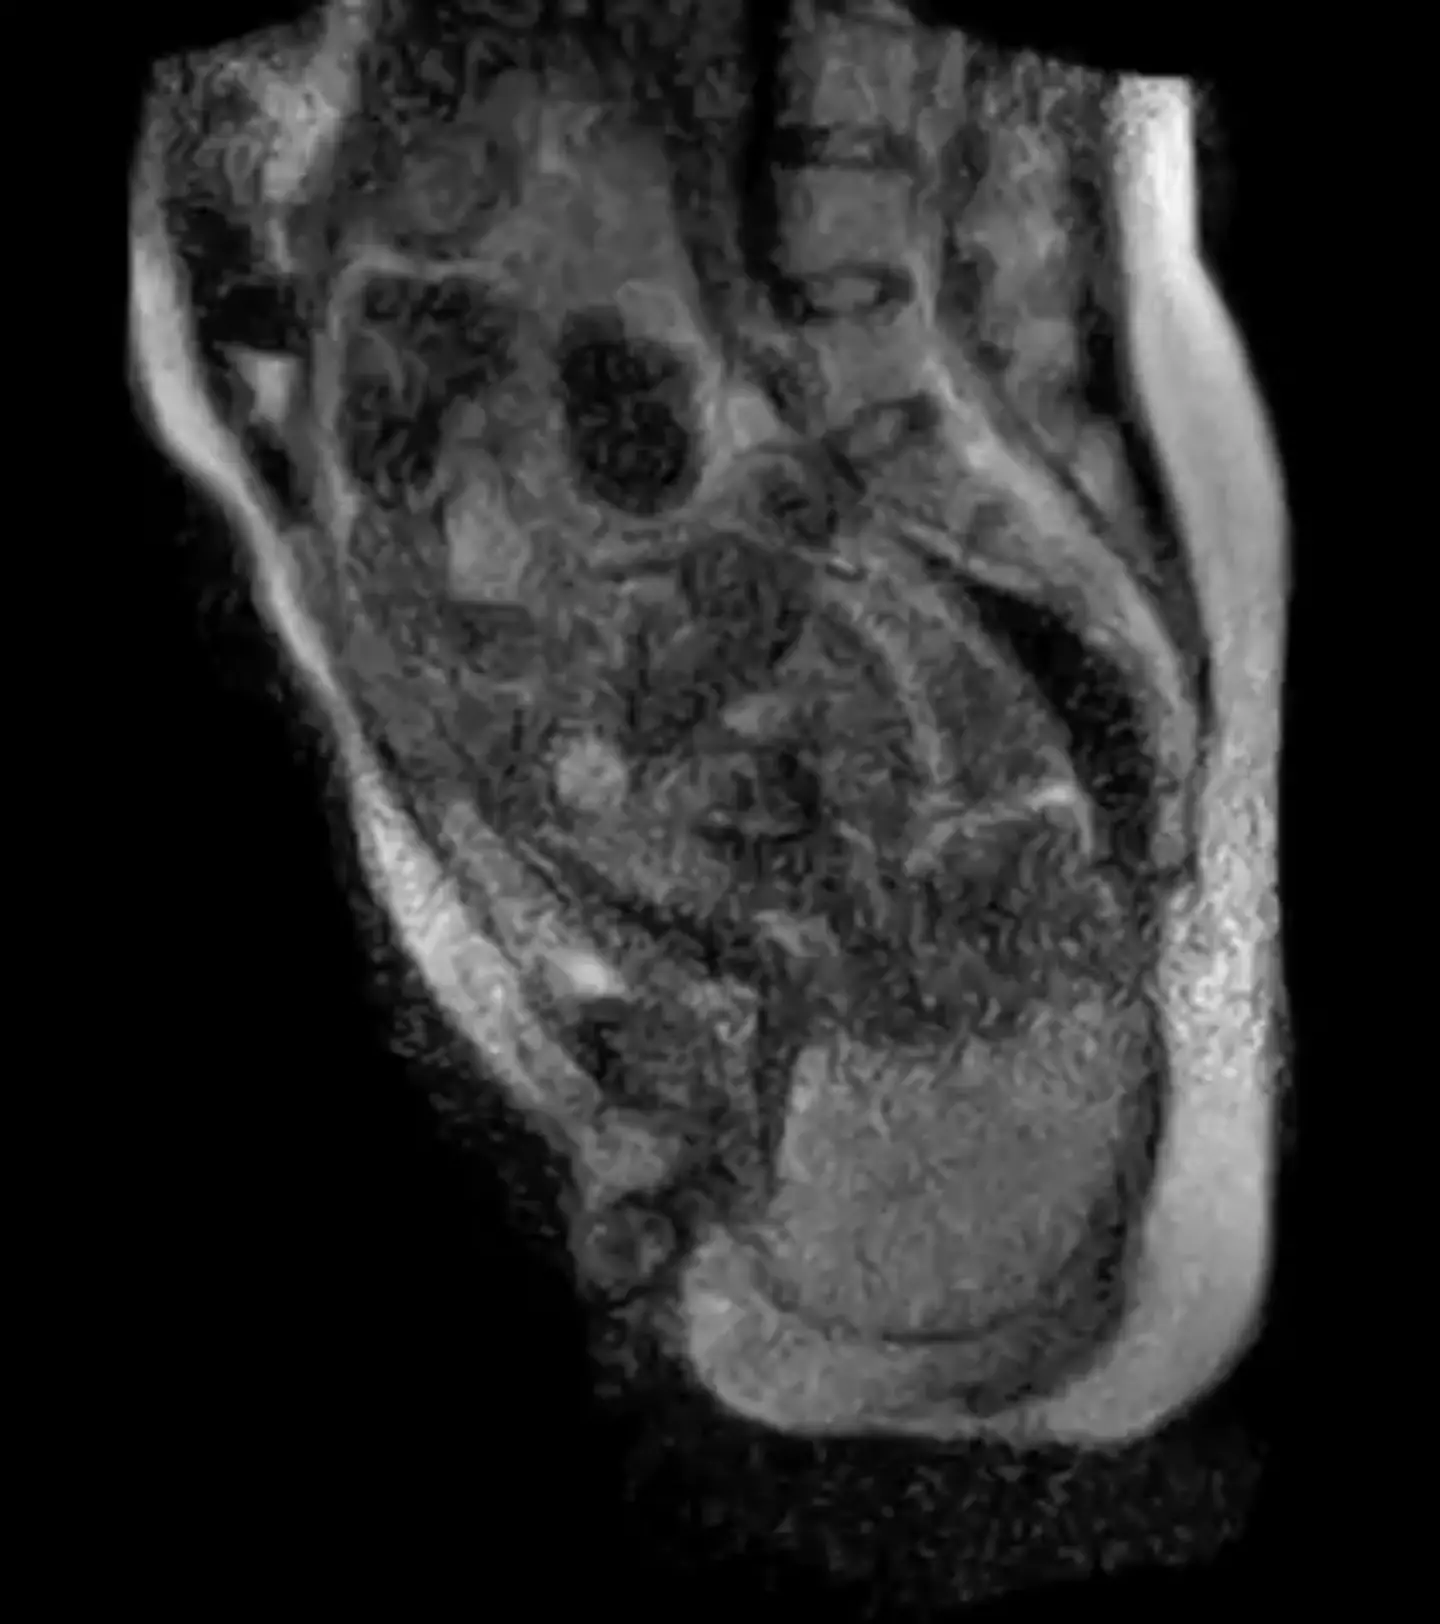

Moving on to what happens nine months after sex, the final 45 minutes of a woman giving birth was captured and sped up as part of a 25-second video, which was made through a number of MRI images taken in the same section of her body.

German researchers from the Charité University Hospital in Berlin carried out what was a medical first, giving us an insight to the inside of a woman's body during labour.

Footage of the birth reveals the exact position of a foetus and its movement through the birth canal, which gave health experts more of an insight into the process.

The short video shows the mother's final push and the baby's head crowning, with the movement of the mum's organs helping to guide doctors during harder deliveries.